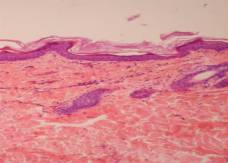

During

the treatment lotion improved skin condition in 83.33% of the rats. Morphological

characteristics AKD were not in 33.3% of these animals (pic. 2а). On other 50%

of the rats was observed (mostly) small, limited both in depth and across the

injury site, covered the crust that is quite easy to flake off. We traced

obvious signs accelerating regeneration of the epithelium in these areas (expressive

as boundary epithelization and from the epithelium of saved hair follicles).

There is no or there is reduced inflammatory cell reaction in the dermis under

the, the condition of the walls and the size of the lumen were normal of most

blood capillaries (pic. 2b).

Рiс

2. Rats skin which were treated with lotion “Mometasone with Ceramides”: а – no

signs of allergic dermatitis; b – limited area of damage, no

inflammatory cell reaction in the dermis, the condition of capillaries is

normal; c – in the dermis condition of capillaries is close to normal,

inflammatory reaction precapillary and subcutaneous tissue is decreased.

Hematoxylin-eosin. х 100.

Spreading

peel outside reduced markedly damage zones. Crust is sequestered often, and

large areas of the skin surface are clean. The thickness of the epithelial

layer is clearly reduced relative to control pathology, signs of acanthosis

were not found. Sometimes there was a temperate spongiosis and vacuolar

dystrophy of epidermocytes. In the dermis condition of collagen matrix,

arteriovenula bridge, the hair follicles are close to normal, inflammatory

reaction is absent or greatly reduced (pic. 2c). Only one rat (16,7%), which

was treated with lotion “Mometasone with Ceramides”, skin condition was a

little different from that of the control rats.